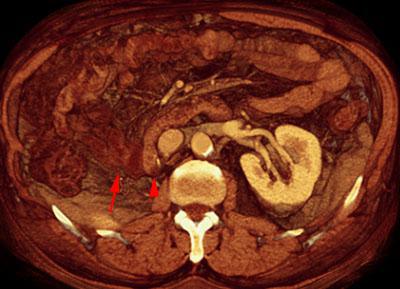

Recidiva adenopática de hipernefroma